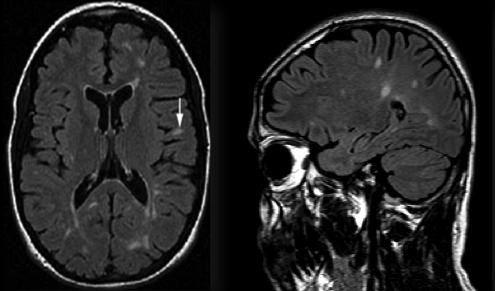

Tipik lezyon lokalizasyonları

- Korpus kallozum lezyonları

- Periventriküler lezyonlar

- Beyin sapı / infratentoriyal lezyonlar

- Jukstakortikal lezyonlar

- Spinal kord lezyonları

Bu bölgelerdeki örnek lezyon alanları, MRG üzerinde İMG – MRG-1’den İMG – MRG-6’ya kadar olan görsellerde gösterilmiştir.

İMG – MRG-1: Tipik T2 lezyonları.

İMG – MRG-2: Korpus kallozum ve periventriküler lezyonlar.

İMG – MRG-3: Beyin sapı / infratentoriyal yerleşim.

İMG – MRG-4: Periventriküler yerleşimli lezyonlar.

İMG – MRG-5: “Kirli ak madde” görünümü.

İMG – MRG-6: Jukstakortikal lezyonlar.